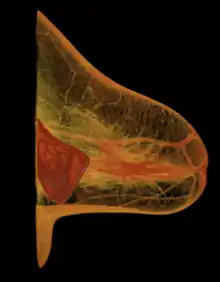

Implant rupture visualized by breast computed tomography

Because a breast implant is a Class III medical device of limited product-life, the principal rupture-rate factors are its age and design; nonetheless, a breast implant device can retain its mechanical integrity for decades in a woman's body.[43] When a saline breast implant ruptures, leaks, and empties, it quickly deflates, and thus can be readily explanted (surgically removed). In some cases, saline implant rupture can result in an infection due to bacteria or mold that had been within the implant, though this is uncommon.[44] The follow-up report, Natrelle Saline-filled Breast Implants: a Prospective 10-year Study (2009) indicated rupture-deflation rates of 3–5 per cent at 3-years post-implantation, and 7–10 per cent rupture-deflation rates at 10-years post-implantation.[45] In a study of his 4761 augmentation mammaplasty patients, Eisenberg reported that overfilling saline breast implants 10-13% significantly reduced the rupture-deflation rate to 1.83% at 8-years post-implantation.[46]

A breast implant failure: the parts of a surgically explanted breast implant are the red, fibrous capsule (left), the ruptured silicone implant (center), and the transparent filler-gel that leaked with the capsule (right).

When a silicone breast implant ruptures it usually does not deflate, yet the filler gel does leak from it, which can migrate to the implant pocket; therefore, an intracapsular rupture (in-capsule leak) can become an extracapsular rupture (out-of-capsule leak), and each occurrence is resolved by explantation. Although the leaked silicone filler-gel can migrate from the chest tissues to elsewhere in the woman's body, most clinical complications are limited to the breast and armpit areas, usually manifested as granulomas (inflammatory nodules) and axillary lymphadenopathy (enlarged lymph glands in the armpit area).[47][48][49]